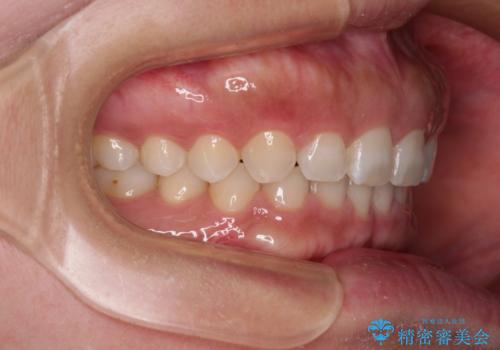

【モニター】ディープバイトを治す ワイヤー装置による矯正治療

- 2年1ヶ月

ディープバイトが改善されたことで、食いしばりしかできなかった状態からスムーズな歯ぎしりができるようになりました。